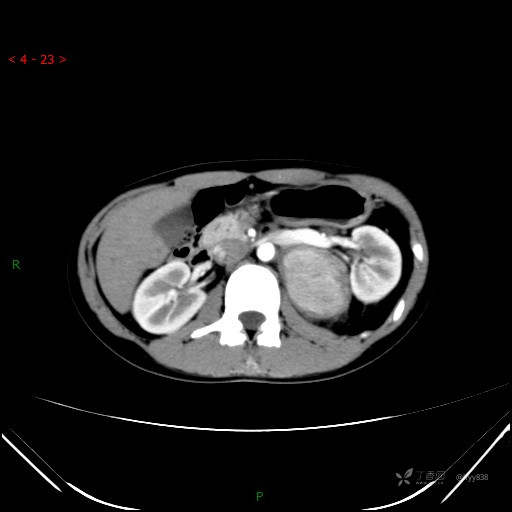

增强动脉期